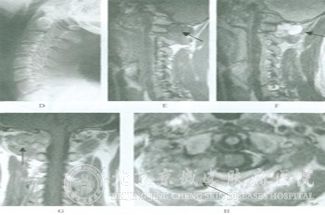

如何诊断神经纤维瘤?神经纤维瘤是常见皮肤病之一,此病具有一定的遗传性,又由于此病患者症状一般表现为较大的瘤体,这两方面的特征给患者的身体及心理造成了很大的影响。严重影响了日常生活与工作,如果我们了解更多有关神经纤维瘤的内容,就可以及时的发现并治疗。那么如何诊断神经纤维瘤呢?

北京京城皮肤医院指出:神经纤维瘤的瘤体一般多数位于肢体,腋窝,也可位于锁骨上,颈等部位;但是位于肢体上瘤全呈梭形,其神经干支配的肢体远侧常有麻木,疼痛,感觉过敏等症状;如果压迫瘤体会有麻痛感。